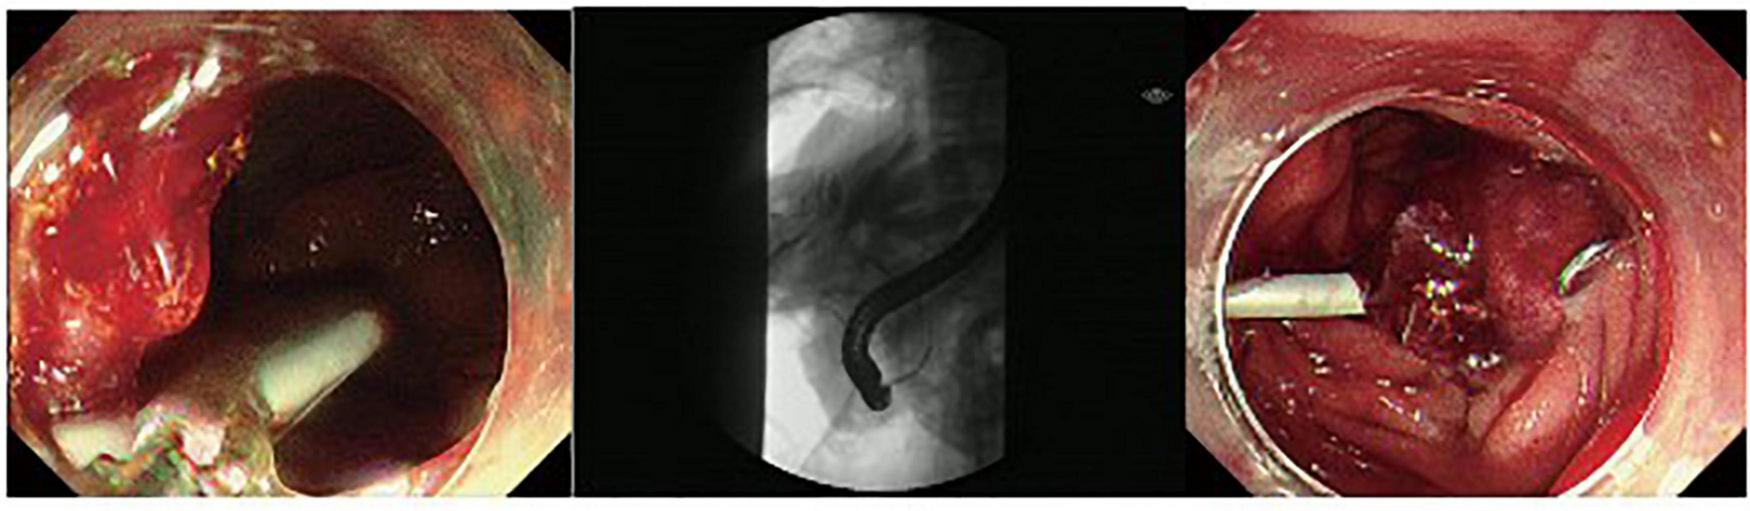

FIGURE 3

A duodenal wall perforation closed by OTSC. The patient received ERBD. The perforation per had signs of peritoneal perforation.

The fundus perforation, the peri-ampullary diverticulum perforation, and eight duodenal perforations were treated by closing the lesion, performing endoscopic nasobiliary drainage (ENBD) or endoscopic retrograde biliary drainage (ERBD), conducting gastrointestinal decompression, and using proton pump inhibitor (PPI), somatostatin (SS), and broad-spectrum antibiotics for 5–7 days. Each lesion was closed by clips, purse string sutures, or over-the-scope-clip (OTSC) (Figures 1–3). Three afferent limb perforations and three duodenal wall perforations were treated through surgery. The small bile duct perforation on the liver surface, the residual duct of gallbladder perforation, and the 26 peri-ampullary perforations were healed through nasobiliary drainage or biliary stenting drainage, gastrointestinal decompression, and using PPI, SS, and broad-spectrum antibiotics for 5–7 days. Biliary stents are typically 8.5 Fr × 7 cm in size, whereas pancreatic stents are typically 5 Fr × 5 cm in size. If no unusual conditions exist, the stents will be removed after 1 month of satisfactory drainage. Three patients received endoscopic retrograde pancreatic drainage (ERPD) at the same time. The 81-year-old female patient with a duodenal wall perforation, which had been closed with OTSC, died of heart failure and post-ERCP pancreatitis 3 days after the ERCP procedure. The other patients recovered successfully (Figure 4). Management outcomes of the 45 patients were summarized in Table 3. The mortality was 2.2% (1/45).